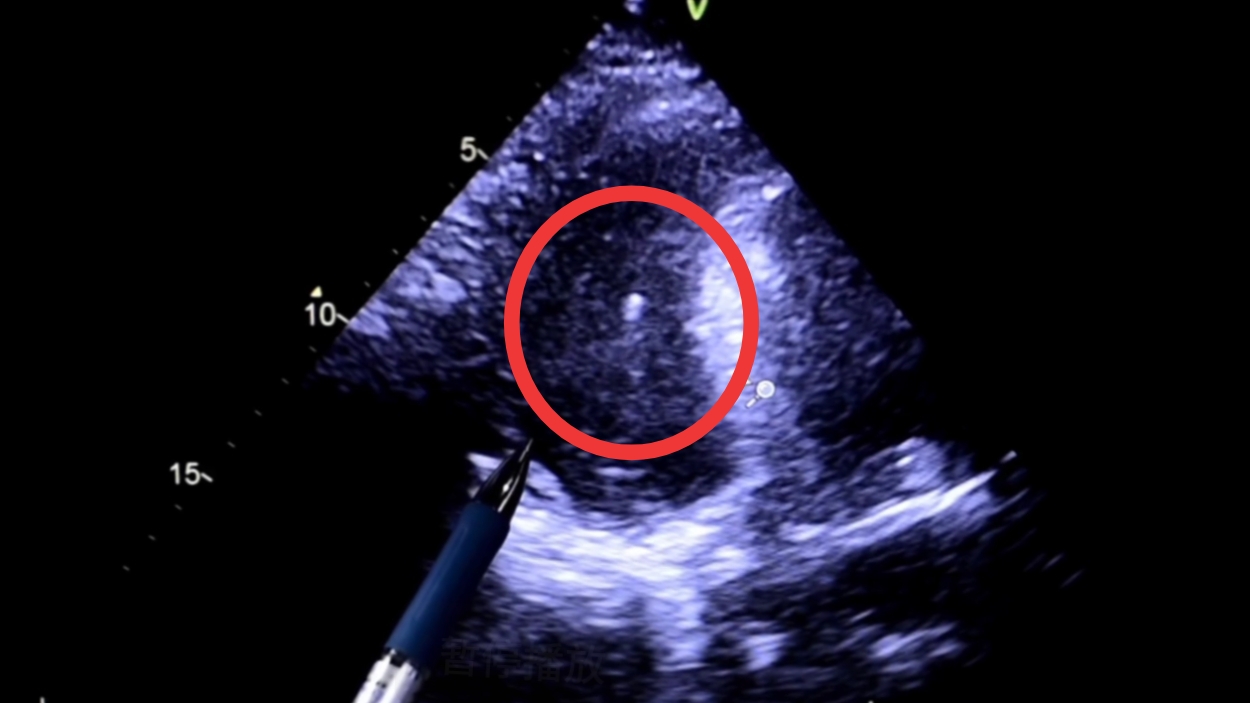

这个图像就是患者当时的心脏。相对颜色比较深的区域,就是大姐的比较局限、位置比较怪异的,心包积液的范围。旁边鼠标所在、比较发亮的区域,是心脏的肌肉,就是心室壁。

沿着超声的指引的方向,一步一步,实时引导,不让针扎到心脏或者其他的一些组织和结构。

这个亮点,就是最后穿到了心包积液里边,针尖所留下的这一个图像,确保了安全、准确、有效的诊疗效果。